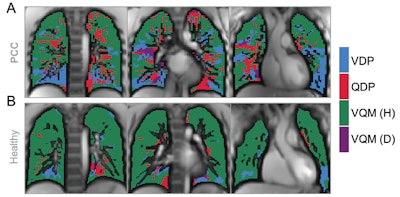

Images show exemplary coronal sections of phase-resolved functional lung MRI defect maps in a pediatric participant with post-COVID-19 condition (PCC) and cardiopulmonary symptoms and a healthy control patient. (A) Images in a 17-year-old male participant with PCC show a ventilation defect percentage (VDP) of 17%, a perfusion defect percentage (QDP) of 16%, a ventilation/perfusion (V/Q) match healthy (VQM [H]) percentage of 64%, and a V/Q mismatch defect (VQM [D]) of 3%. (B) Images in a healthy control participant, with a ventilation defect percentage of 9%, a perfusion defect percentage of 5%, a V/Q match healthy percentage of 86%, and no V/Q mismatch defect. Images and caption courtesy of the RSNA.